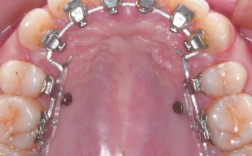

矫治装置粘接(30-60分钟)

根据患者需求选择矫治器:传统金属托槽性价比高,适合复杂病例;陶瓷托槽美观性好;隐形矫治器则需通过3D打印设计个性化附件,粘接时需精准定位,确保牵引方向与阻生牙长轴一致,避免牙齿移位时发生倾斜或旋转。

在局麻下于阻生牙牙冠顶部切开黏膜,去除部分骨质,暴露牙冠并粘接牵引钩,随后用镍钛丝或橡皮圈将牵引钩与矫治器连接,施加轻柔持续的力量(50-70g),每周复诊调整牵引方向,牵引过程中需密切观察牙根吸收情况,若出现明显吸收,需暂停牵引或调整力值。